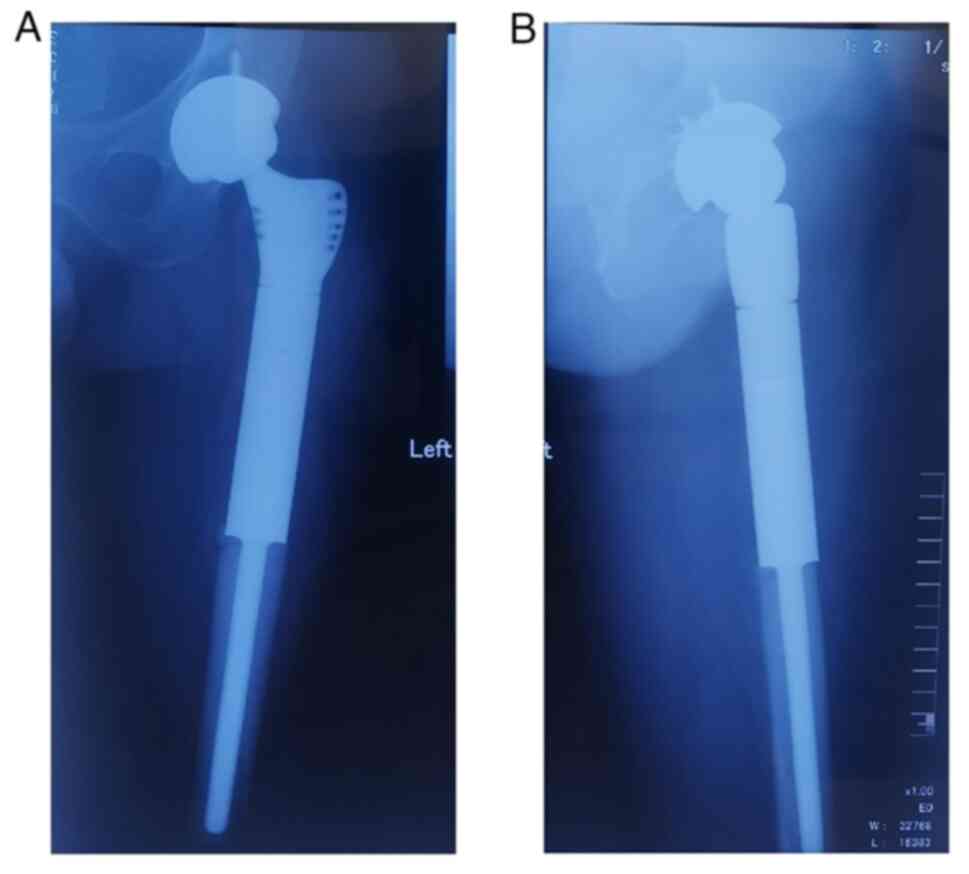

Malignant transformation of an aneurysmal bone cyst of the femoral neck: A case report

Aneurysmal bone cyst (ABC) is a benign, distending, osteolytic and locally aggressive bone tumor that is mostly associated with trauma. Approximately 1% of bone tumors are ABCs, which are most prevalent in adolescents and are usually detected in the spine and long tubular bones. The diagnosis of ABC mainly relies on histopathology, malignant transformation is rare, and the chance of malignancy increases if there are multiple recurrences. Due to the rarity of reports of malignant transformation of ABCs into osteosarcoma, there is still considerable debate on the appropriate treatment strategy. The current paper presents a case of aneurysmal bone cyst malignant to osteosarcoma and the therapeutic measures to provide expertise for the diagnosis and treatment of ABCs that are malignant to osteosarcoma.